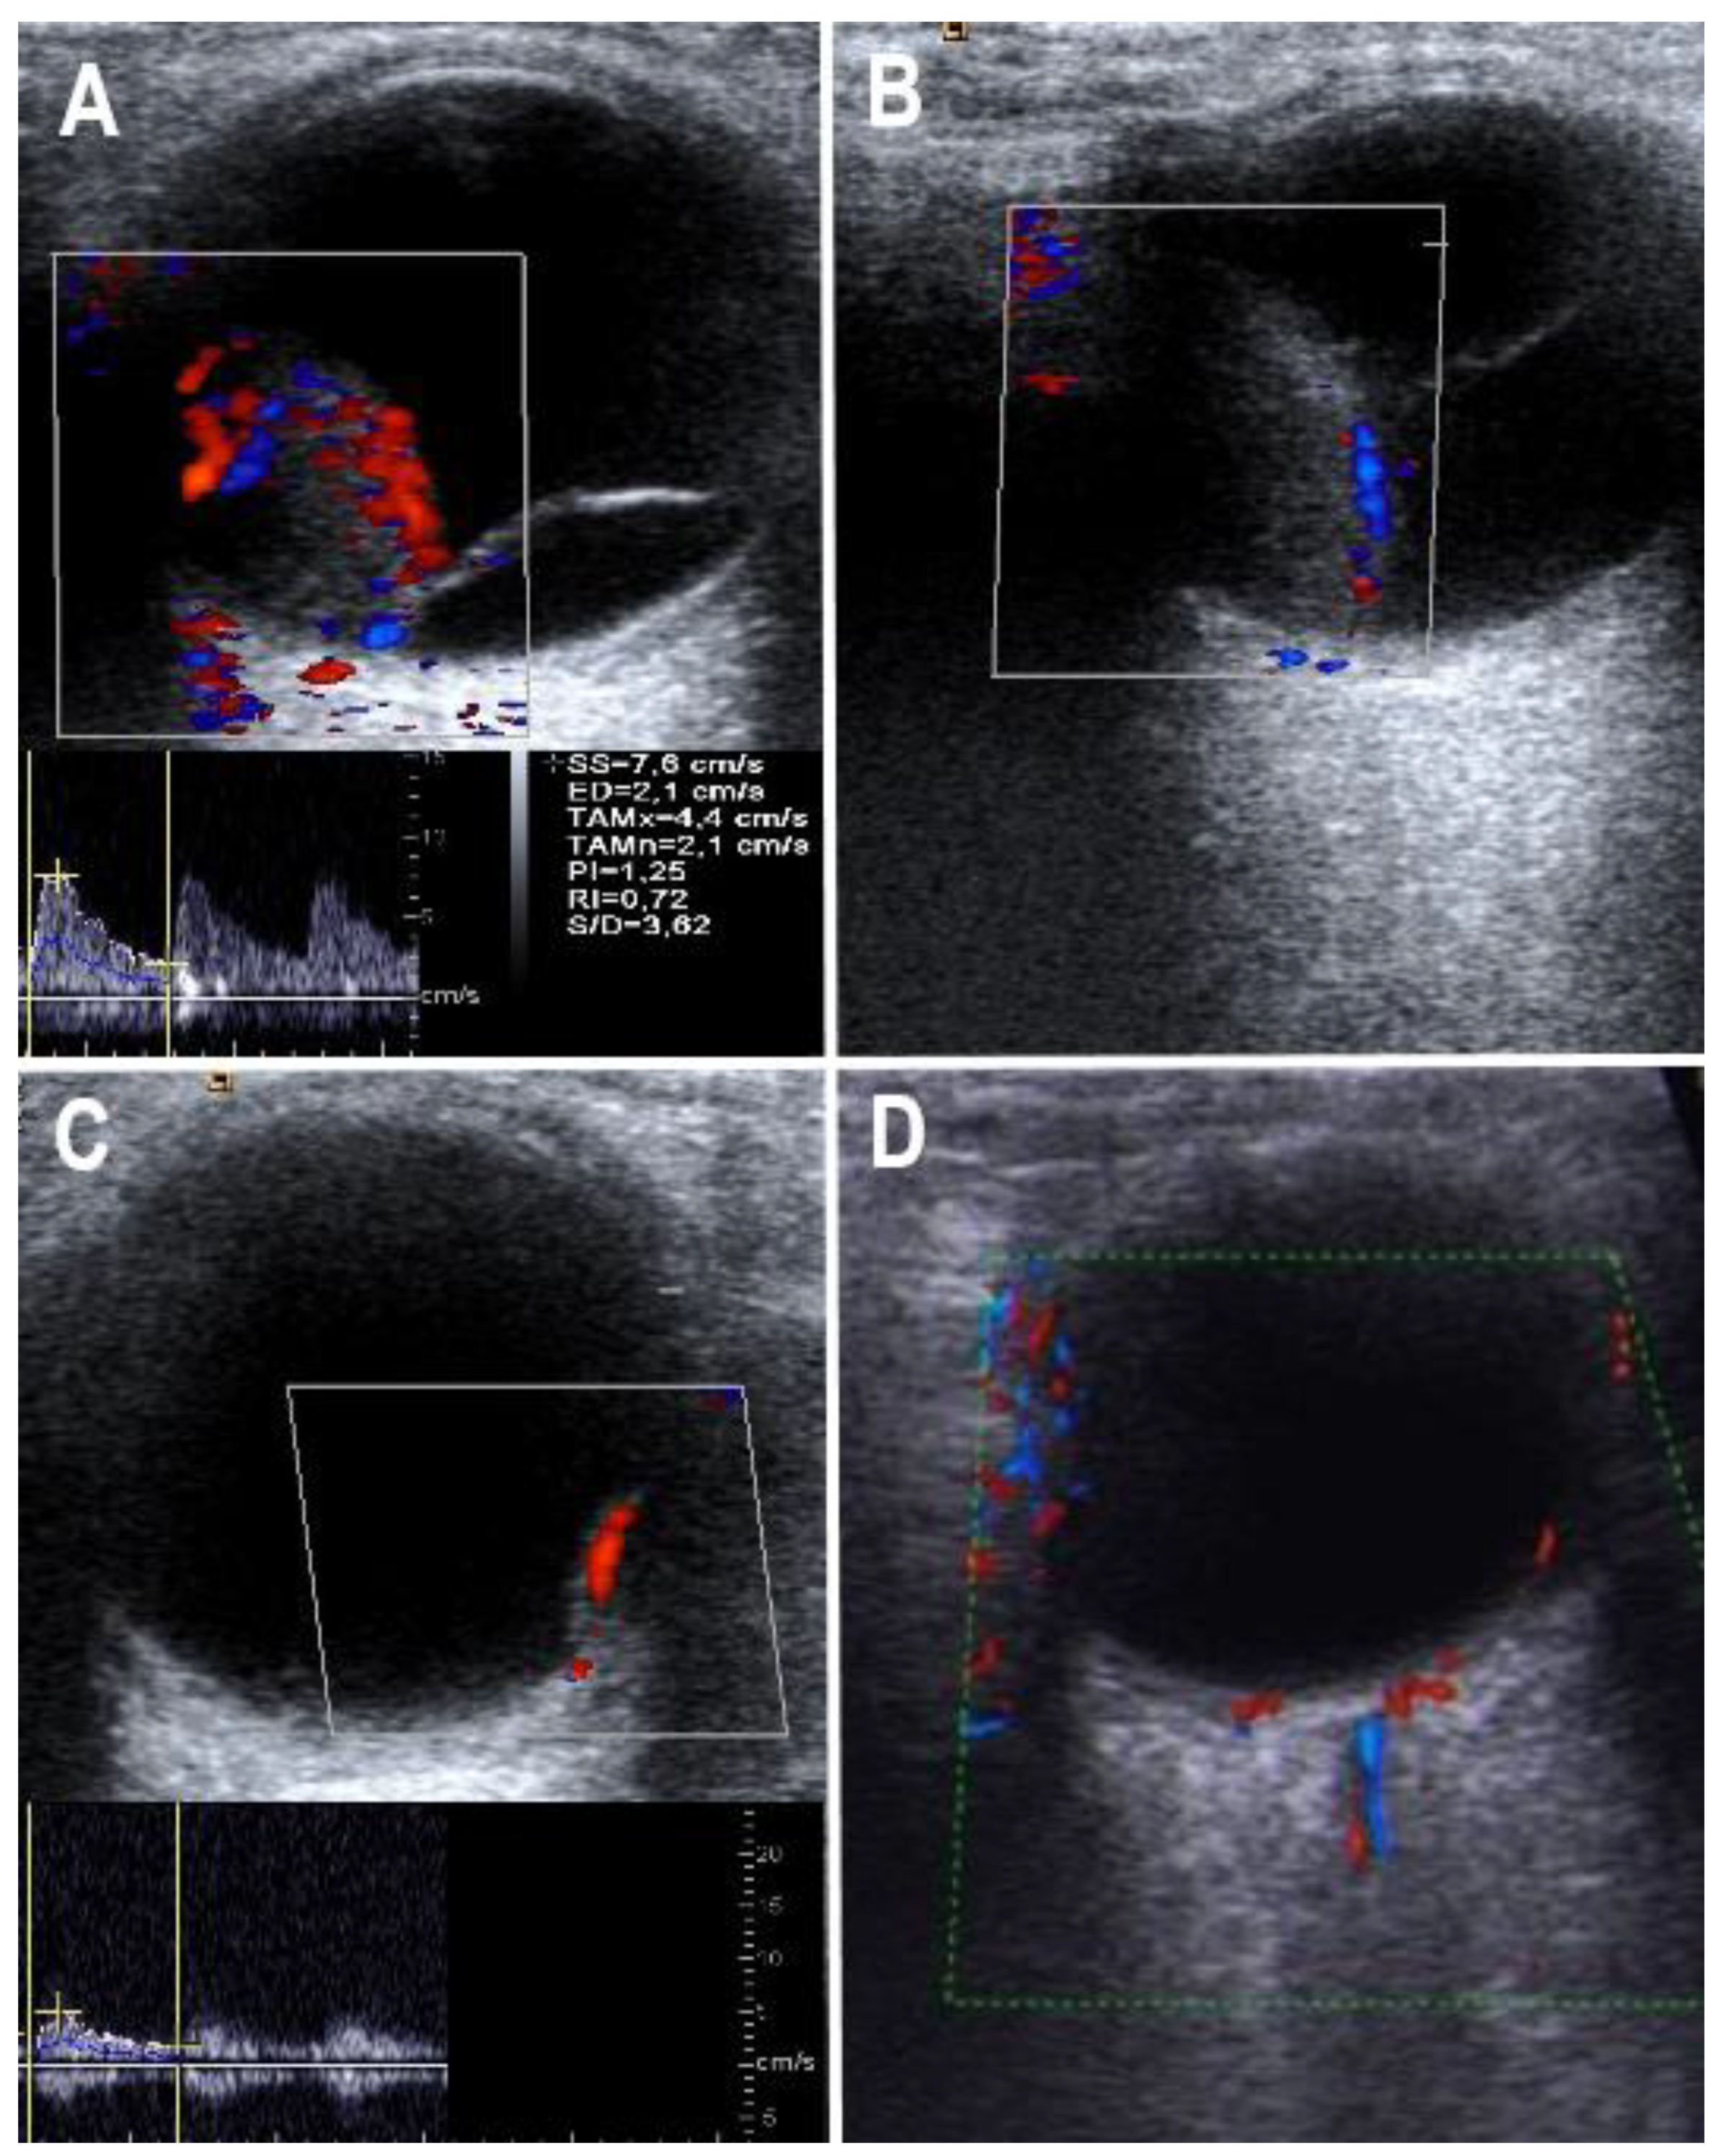

| 0 | No vascularization |

| 1 | Low vascularization (a small internal artery can be visualized) |

| 2 | Moderate vascularization (two to three internal arteries can be visualized) |

| 3 | Strong vascularization (paying, partly strong internal arteries can be shown) |